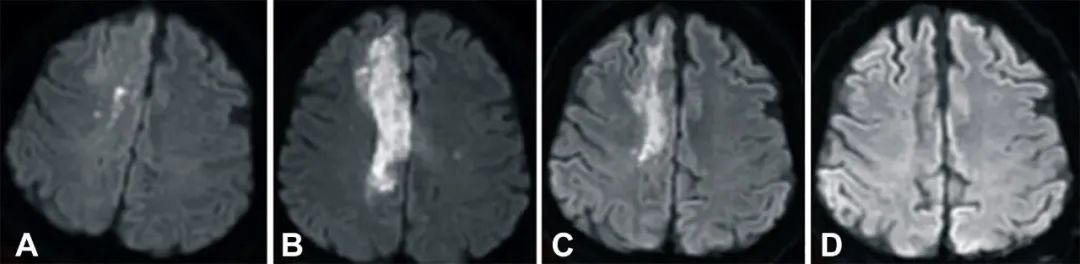

2021年12月23日,中国台湾的一所大学报道了一个案例:一名缺血性脑卒中偏瘫患者在接受脐血干细胞治疗后,12个月内取得完全康复。结果发表在《Cell Transplantation》(细胞移植)期刊上。 患者为40岁男性,该患者有高血压和终末期肾病血液透析病史,在急诊科就诊时表现为急性左侧偏瘫,经检查发现右侧颅外段颈内动脉区域发生脑梗塞。 患者中风发作后第8天接受脐血干细胞输注,又过了8天出院,并在 1、3、6 和12个月随访以评估NIHSS评分、神经功能和MRI结果。 输注后,患者的神经功能逐渐改善。在 12 个月时,NIHSS 评分(A)从 9 分降到 1分,Berg 平衡量表评分(B)从 0 分增加到 48 分,Barthel 指数评分(C)从 0 分增加到 90分。 NIHSS 是用于评估卒中引起的功能损害程度,Berg 量表是用于评定平衡功能,Barthel 指数是对患者日常生活活动的功能状态进行测量,这三个量表都是脑卒中康复评价工具。 中风后 2 小时、8 天进行的弥散加权成像(DWI)显示右侧放射冠有梗死(白色强度增加),3 个月后开始退散,6 个月后消失(A到D)。 梗死发生后 2 小时、8 天、3 个月和 6 个月获得的 T2 加权图像显示右侧放射冠的白色强度增加(A到D)。 结果表明,接受 HLA6/6匹配的脐静脉血液来源的单个核细胞输注之后,这名缺血性卒中成年患者在短时间内明显康复。 与成人外周血相比,围产期来源的脐血中含有更丰富的造血祖细胞和众多的内皮祖细胞,在体内外具有很强的增殖能力。 同时,围产期来源的脐血中大量的 EGF、VEGF、G-CSF 和 IL-10 等细胞因子不仅可以恢复免疫稳态,还可以增强受损大脑的修复能力。 脐静脉血液来源的单个核细胞已经被证明在中风急性期和亚急性期的动物模型中,能发挥强大的治疗作用。除了再生能力以外,这些细胞还具有免疫调节和抗炎作用。因此,它们可以保护脑组织免受中风后炎症引起的继发性损伤。这项研究还使用了甘露醇,帮助脐血单个核细胞更好的穿透血脑屏障,增强神经营养因子和神经生长因子的表达。 这一案例中,患者的康复令人印象深刻,可能与中风后第8天就接受治疗有关。 干细胞治疗脑卒中临床研究进展 一旦发生脑卒中,会有大量的神经细胞死亡,而受损的神经功能难以自我修复,留下严重的后遗症(口眼歪斜、面部扭曲、语言不利、行动障碍等),给家庭乃至社会带来沉重的负担。 干细胞具有自我复制和多向分化的潜能,可分化为神经元或其支持结构,为其移植治疗脑卒中提供了广阔的前景。 2021年6月14日,《干细胞转化医学》发表的一项美国Ochsner-LSU健康科学中心的临床研究报告显示,干细胞强大的旁分泌功能,对减轻脑卒中后损伤和改善神经功能障碍具有良好的保护作用。 2020年5月15日,来自台湾大学的学者发表了一篇《Potential of stem cell therapy in intracerebral hemorrhage》研究文章,综述了PubMed上100多篇英文出版物(干细胞治疗脑出血或出血性中风的文章和评论)。收集的临床研究数据表明,干细胞治疗能有效改善脑出血后的功能恢复。干细胞治疗的可能机制包括细胞替代、促进内源性神经再生、抗凋亡、免疫调节等。 2019年初,休斯顿大学健康科学中心招募了110位缺血性脑卒中患者参与向脑内注射干细胞的临床研究,此疗法已进入临床II期试验。其中对脑出血病程为1-3月的20例患者进行干细胞移植,术后2年随访,发现经干细胞移植的患者肌张力改善最为明显,肌张力均有所下降,语言表达能力有所改善,吐字清晰。干细胞对脑卒中患者的预后程度优于未经干细胞移植同期脑出血的患者。 2019年,解放军总医院在《干细胞转化医学》(Stem Cells Translational Medicine)杂志上公布,干细胞移植有助于脑卒中偏瘫患者运动功能的恢复。9名年龄在30-65岁之间的偏瘫患者参与了这项临床研究,他们在中风后5-24个月接受人源神经干细胞NSI-566脑内移植(移植至脑内梗塞灶附近)。结果表明,人源神经干细胞NSI-566治疗偏瘫性脑卒中拥有一定的临床益处。 众多临床研究表明,干细胞能减少神经功能缺损、减少梗塞面积、减少炎症以及增加神经发生和血管生成。随着临床试验的进展,相信干细胞技术有望帮助千千万万的脑卒中患者尽快康复。